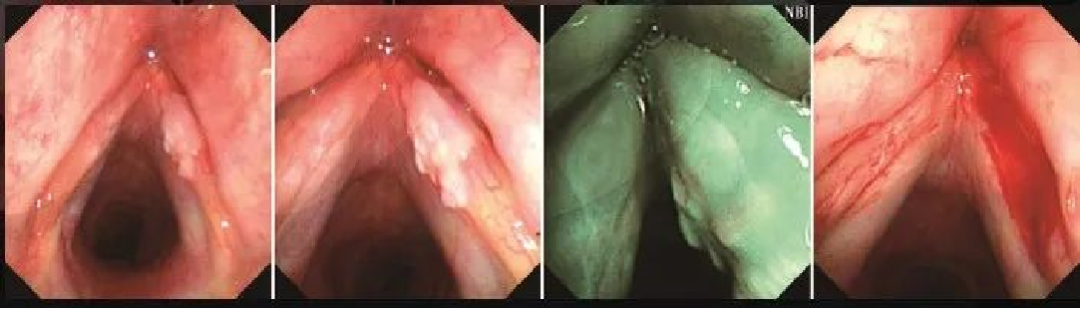

声带任克水肿

声门区右侧声带中部隆起,黏膜充血,表现似囊肿,内镜下将囊液放出,囊壁取活检送病理。左侧声带水肿明显,全段呈鱼腹状。NBI模式下可见黏膜表面有墨绿色黏膜下血管及棕褐色斜行血管,未见IPCL扩张。